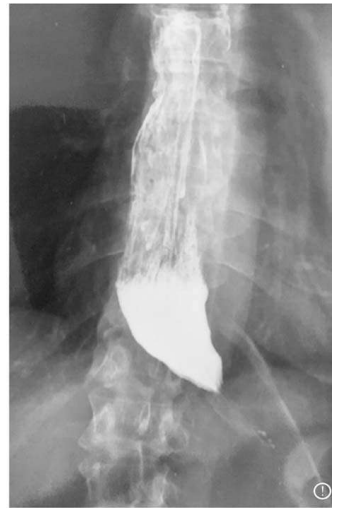

Considerando a figura acima, assinale a alternativa que apresenta a opção terapêutica que está fora do padrão de tratamento para essa situação, em paciente com exame endoscópico com esofagite e nunca tratado previamente.

Quanto à realização de uma fundoplicatura para a correção da doença do refluxo, assinale a alternativa correta.